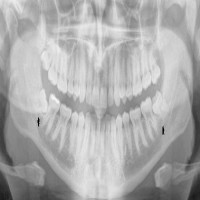

دندان عقل معمولاً آخرین دندانی است که در سنین ۱۷ تا ۲۵ سالگی رشد می‌کند. در بسیاری از افراد، فضای کافی برای رشد صحیح دندان عقل وجود ندارد؛ به همین دلیل ممکن است به صورت نهفته یا نیمه‌نهفته باقی بماند، باعث درد، التهاب لثه، پوسیدگی دندان‌های مجاور یا حتی آسیب به عصب فک شود.

•    ارزیابی دقیق با اسکن دیجیتال و CBCT

•    مشاوره تخصصی و بررسی دقیق عکس رادیولوژی